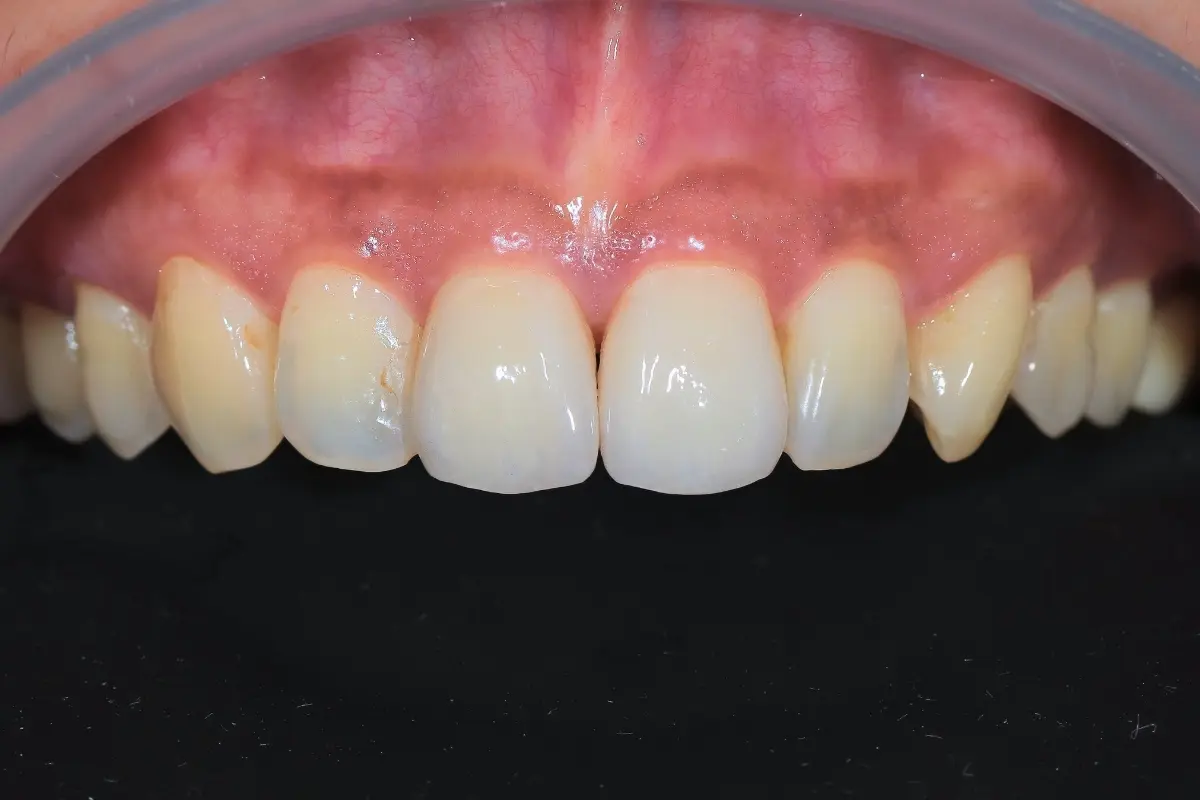

Dentist 陳昕 全口照護醫師 看診項目 前牙美學仿生樹脂補牙/全科牙醫 學經歷 臺北醫學大學牙醫系學士 前天主教新店耕莘醫院醫師 前臺北榮民總醫院醫師 亞洲齒列再生研究學會Advance植牙補綴專科訓練 微光私塾牙周雷射微創治療技術訓練 臺灣牙醫顯微美學治療學會會員醫師 中華審美牙醫學會會員醫師 CASE 案例分享 滲透型樹脂修復 主治醫師 陳昕 治療時間 單次療程 主訴 想處理前牙白白的色斑 前牙美學/仿生美學樹脂 主治醫師 陳昕 治療時間 單次療程 主訴 牙齒整齊,但門牙中間縫隙明顯,影響笑容美觀 前牙美學/陶瓷貼片 主治醫師 陳昕 治療時間 約1個月 主訴 兩顆門牙缺角,想要重建外觀 前牙美學/滲透型樹脂修復 主治醫師 陳昕 治療時間 單次療程 主訴 門牙有長期存在的白斑與表面不平整,影響外觀與自信 前牙美學/仿生美學樹脂 主治醫師 陳昕 治療時間 約兩週 主訴 矯正後的黑三角縫問題 前牙美學/仿生美學樹脂 主治醫師 陳昕 治療時間 約三週 主訴 因牙周病產生的黑三角縫 前牙美學/牙冠增長術、仿生全瓷牙冠 主治醫師 陳昕 治療時間 約6個月 主訴 牙齒排列不整、假牙外觀不自然 前牙美學/仿生美學樹脂 主治醫師 陳昕 治療時間 約兩週 主訴 露齒笑時黑三角縫明顯,覺得不好看 前牙美學/仿生美學樹脂+噴砂美白 主治醫師 陳昕 治療時間 約兩週 主訴 露齒笑時有不好看的黑三角縫,容易有茶垢沉澱,讓縫隙更明顯 牙齒美白/噴砂美白+冷光美白 主治醫師 陳昕 治療時間 單次療程 主訴 前牙泛黃且染色明顯,影響外觀與自信 牙齒美白/噴砂美白 主治醫師 陳昕 治療時間 單次療程 主訴 牙齒表面有喝咖啡、抽菸造成的外部染色,影響外觀與自信 點此載入更多 Column 精選文章 FEATURED 精選案例 【牙科修復案例】陶瓷貼片可以做一顆嗎?單顆門牙缺角修復,陶瓷貼片重建自然笑容 2026-01-16 從「假笑」到「自然笑容」的轉變——認識「牙冠增長術」與「仿生全瓷冠」 2025-10-14 Video 精選影音